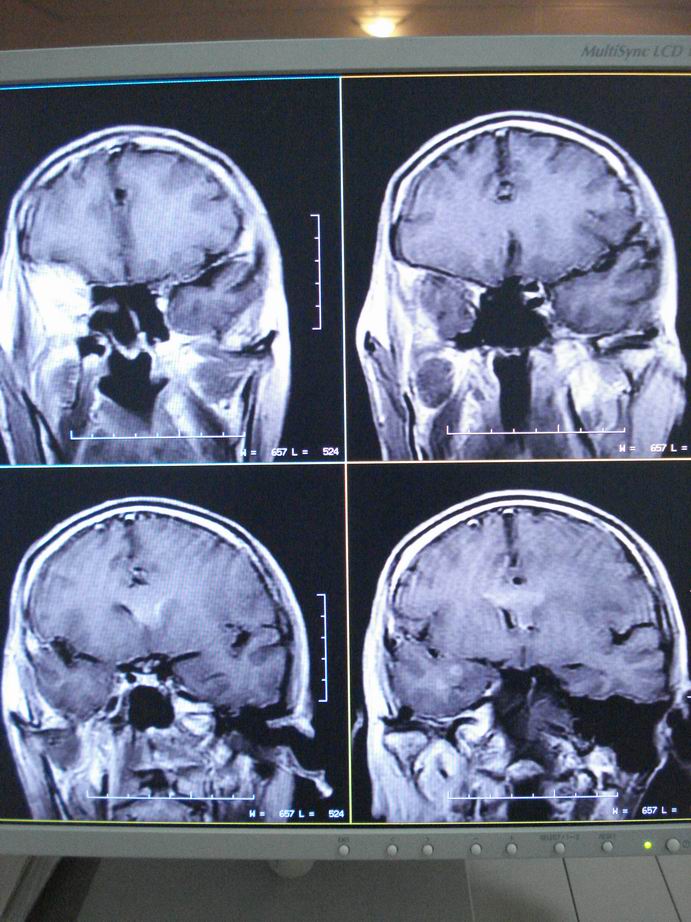

男60岁,左侧肢体乏力及精神异常10天,血压正常,血常规,肝肾功正常,腰穿无异常,请教颅内多发病灶,考虑什么?感染?肿瘤(转移性?)还是其它?

考虑为颅内多发转移瘤

脑内多发性转移瘤。

淋巴瘤较转移瘤可能大。

脑内多发占位性病变,首先考虑感染性病变,其次是转移瘤。

结合病人高龄,考虑转移瘤